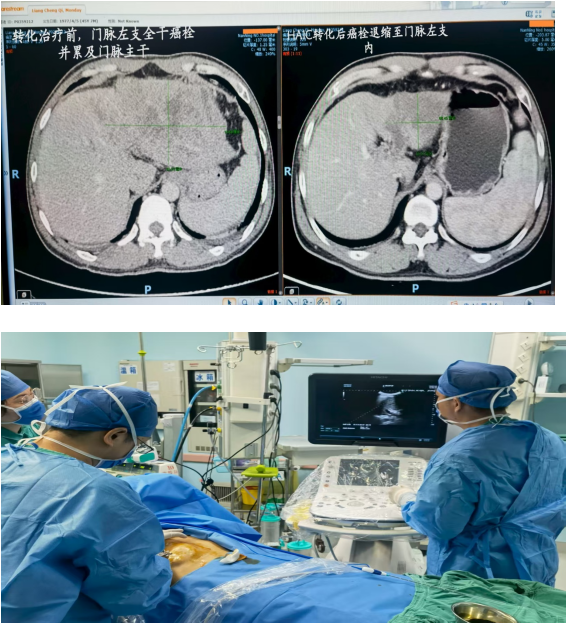

四、肝癌手术切除及介入靶免转化综合治疗

作为中国肝癌防治联盟肝癌防治体系推进单位,我科致力于肝恶性肿瘤综合救治。我科开展肝恶性肿瘤的腹腔镜微创及开放手术,并在全区率先开展晚期肝癌的介入及靶免转化系统治疗,部分经转化治疗癌灶缩小、脉管癌栓退缩降期后并成功手术切除,取得了较好的肿瘤控制效果,延长了晚期肝癌患者的生存时间并提高了其生存质量。针对部分小肝癌及复发癌灶,实施超微创的微波消融治疗。